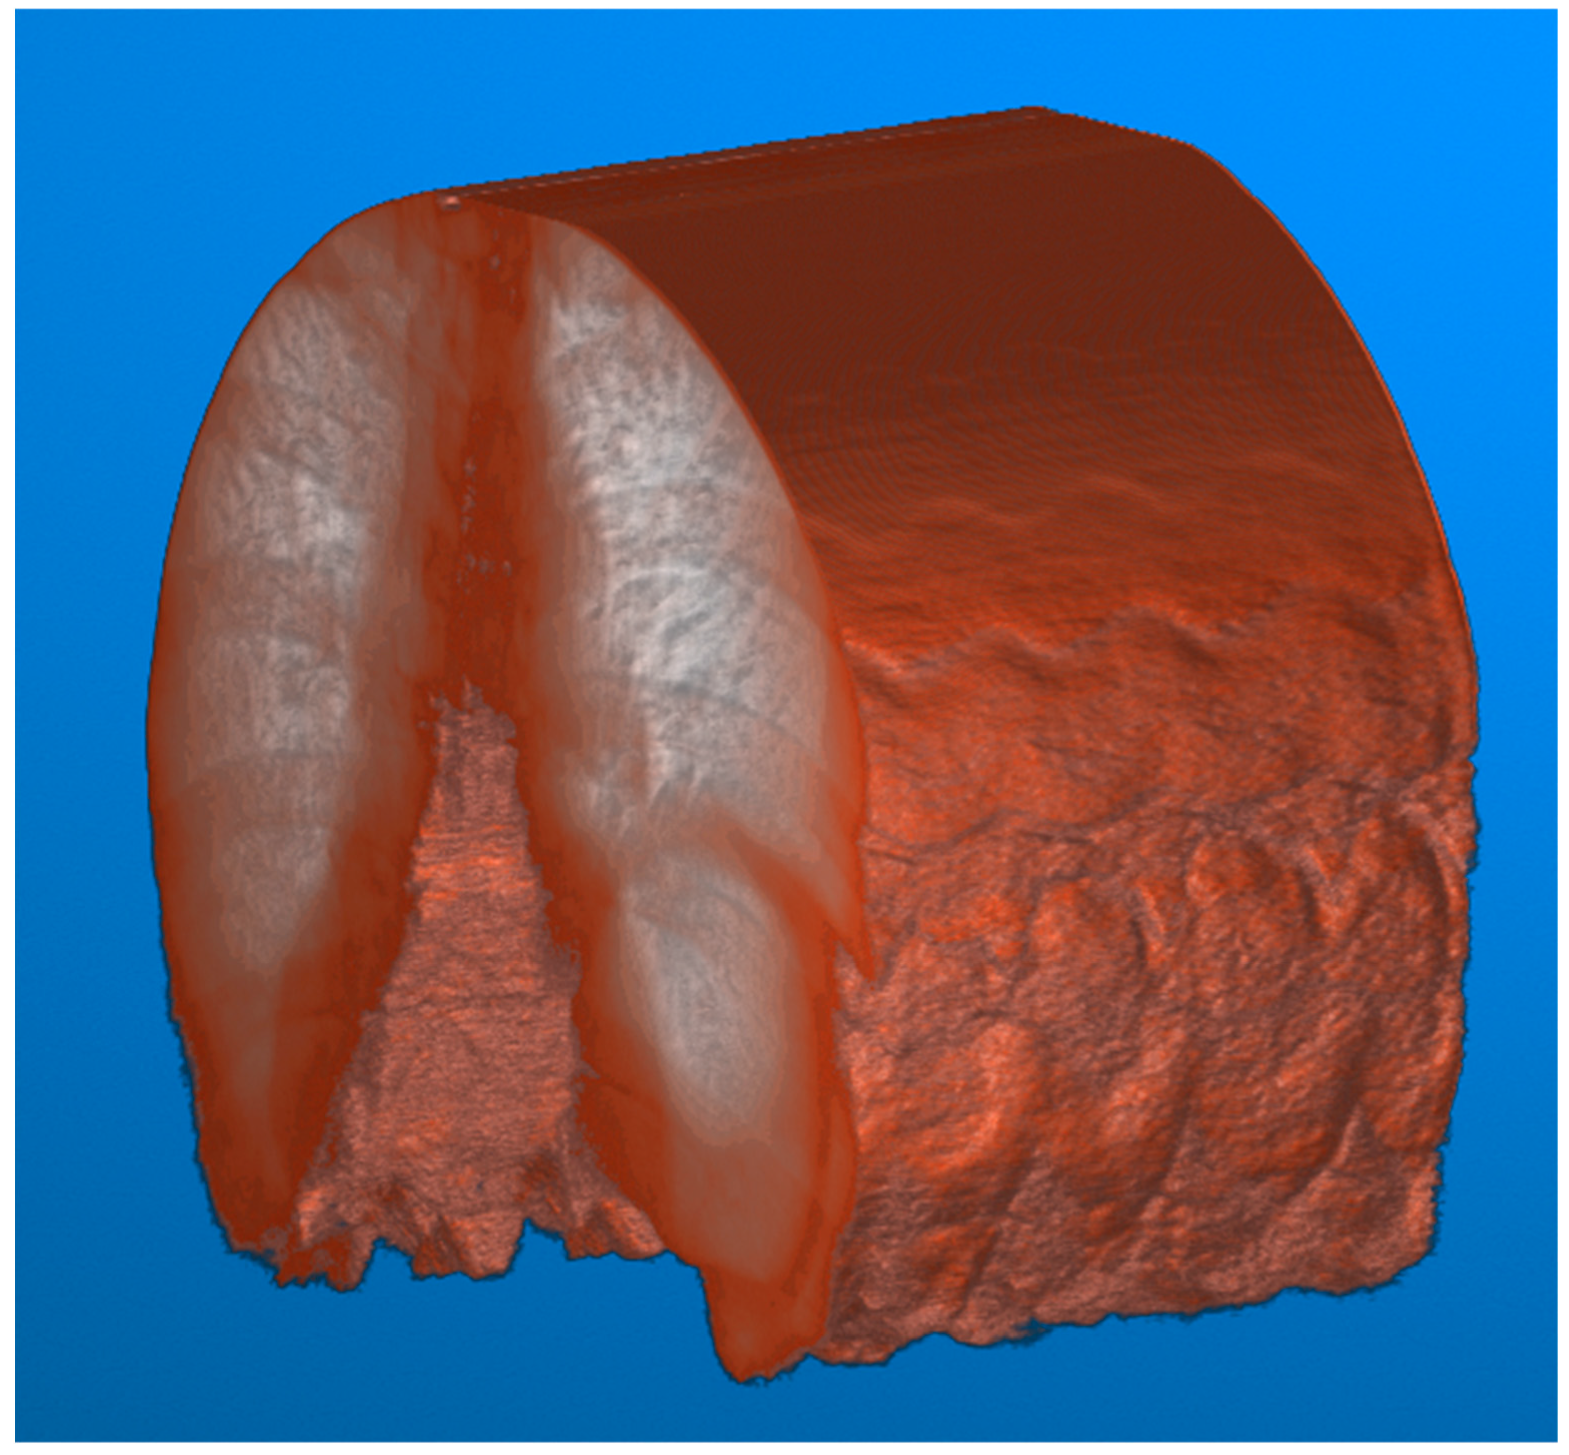

The resulting imagery (Figure 9) demonstrates a potential expected difference between calibrated and non-calibrated imagery for the analysis of diaphragm motion. The distortion varies based on the movement of the diaphragm, with maximum distortion found at the contraction and relaxation of the diaphragm. The imagery (Figure 9) showcases the effects of distortion represented as the green overlay (left) and gray (right). This distortion can result in a difference of 10 pixels or more between calibrated and non-calibrated imagery.

The calibration of fluoroscopic Imagery was further demonstrated in its impact on the quantitative diagnosis of hemidiaphragm paralysis and detection of paradoxical diaphragm motion [19]. Specifically, significant differences between calibrated and non-calibrated imagery can be observed in the position of the diaphragm at peak contraction and relaxation as visualized by the peaks and troughs of the periodic motion of regular breathing (Figure 9). This difference could potentially skew the significance and confidence in any paradoxical motion.

Figure 9. Video fluoroscopy from a case study of chronic left hemidiaphragm elevation [19] during normal inspiration of the right hemidiaphragm. The image volume is sliced along the y–z plane at a point near the diaphragm to visualize its movement. The geometric distortion coefficients were applied as a calibration to each frame within the video fluoroscopy. The resulting imagery is superimposed (left) and differenced (right). The distortion is most evident at peaks and troughs corresponding to the relaxation and contraction of the diaphragm, respectively.